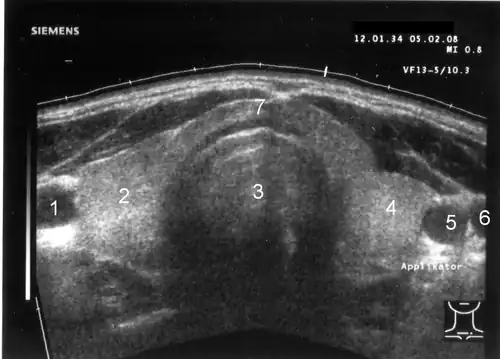

1 Arteria carotis communis rechts, 2 rechter Schilddrüsenlappen, 3 Trachea, 4 linker Schilddrüsenlappen, 5 Arteria carotis communis links, 6 Vena jugularis interna links, 7 Isthmus (Gewebebrücke zwischen rechtem und linkem Schilddrüsenlappen)

Lateral der Schilddrüse sind die Arteria carotis communis (rund, pulsierend und kaum komprimierbar) und die Vena jugularis interna (sichelförmig, leicht komprimierbar) erkennbar. Links hinter der Schilddrüse lässt sich die Speiseröhre abgrenzen. Weitere Orientierungsstrukturen sind rechts und links der Musculus sternocleidomastoideus sowie die Vorderkante der Wirbelkörper der Halswirbelsäule.